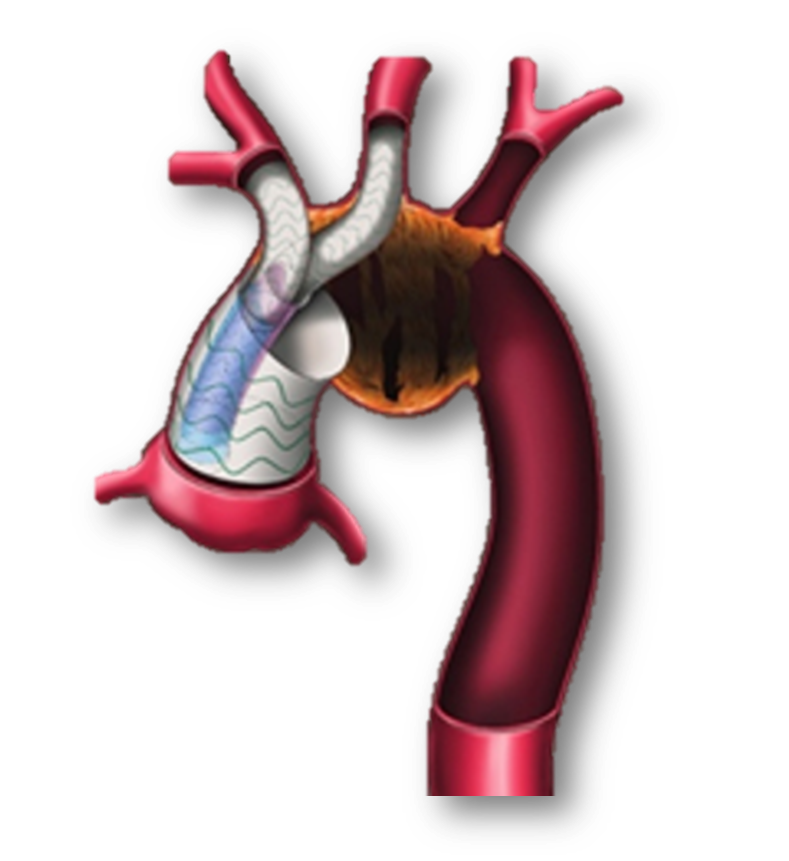

开放手术方法和器材的改进——Fontus术中单分支支架

传统痛点:处理累及左锁骨下动脉(LSCA)的病变时,需在深低温停循环下于LSCA远端吻合,延长停循环时间,增加脑损伤风险。

创新方案:使用Fontus单分支支架,可在常温或浅低温下直接重建LSCA,显著缩短停循环时间。

复杂病例拓展:成功用于既往接受过“烟囱支架”植入后发生逆撕A型夹层的患者。通过开窗技术将漂浮的烟囱支架拉出,再与单分支支架人工血管段吻合,避免了深部远端吻合。

Fontus术中单分支支架